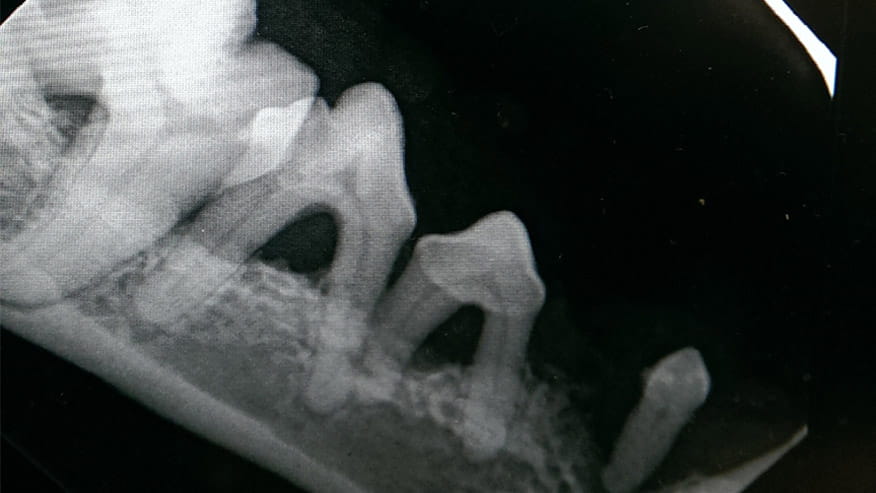

• Our hospital offers dental radiographs (x-rays) as part of our dental care services. Specifically designed dental radiology equipment allows your veterinarian to view structures that lie below the gum line. The location of tooth root infections, the extent of periodontal bone loss and the identification of bone cysts and tumors can be identified using dental x-rays.... Read more

• VCA Wakefield Animal Hospital Dental X-Rays